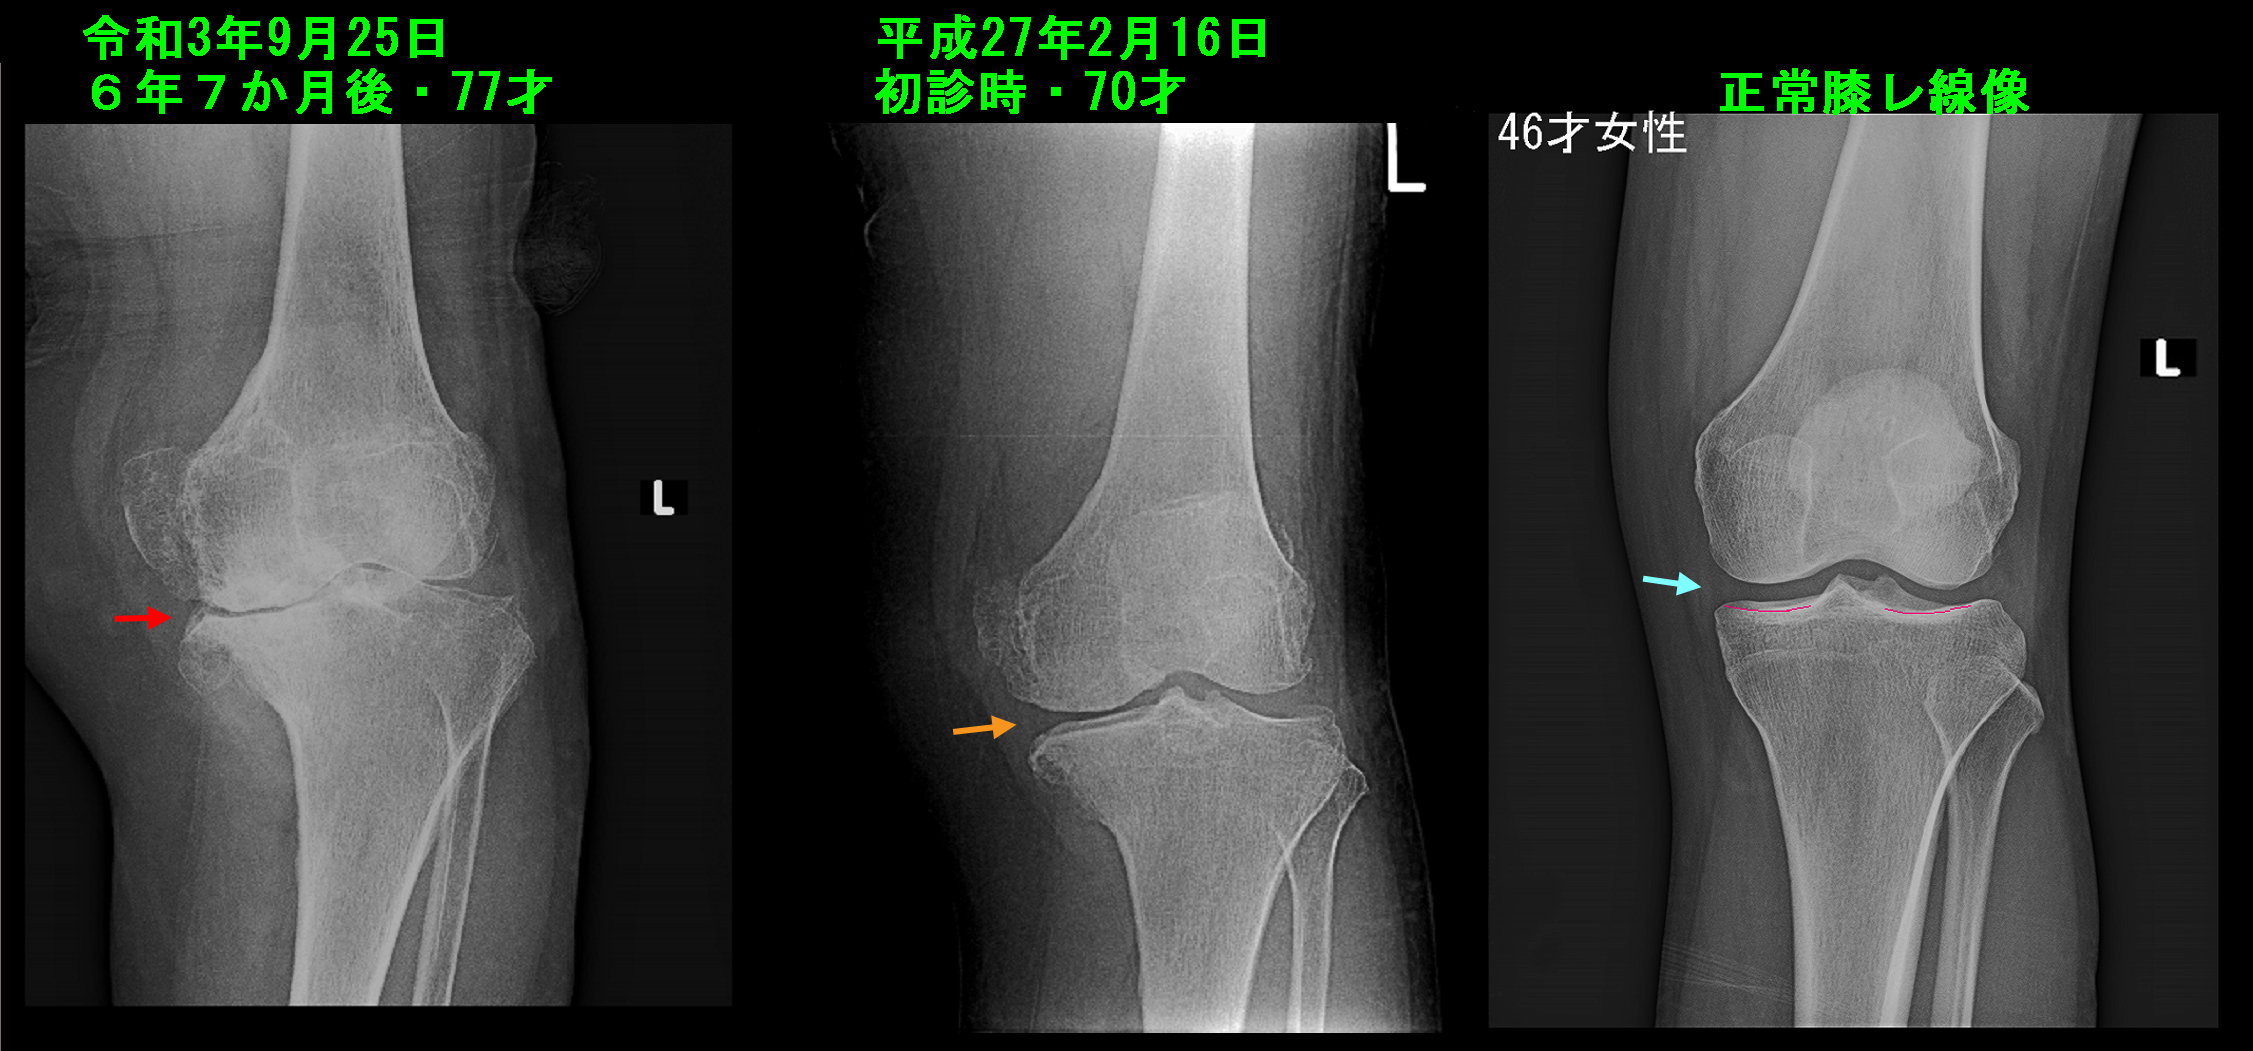

この患者さんは6年前の平成27年2月16日に左膝痛で当院を受診されていました。当時2年前からの左膝痛で正座が困難となったということで、当院で変形性膝関節症の治療と正座ができるためのリハビリテーションを6月5日まで継続し、正座が可能となったということで通院を終了されています。

77才女 Xp1.jpg

上図右端は46才女性の正常の膝関節レントゲン像となりますが、内側と外側の関節の隙間(関節裂隙=れつげきと言います)はともに幅が確保されていて、このスペースに半月板・大腿骨と脛骨の関節軟骨が存在しています。薄青矢印は内側の関節裂隙となります。中央の平成27年2月の患者さんの左膝のレントゲン像ではオレンジ矢印の内側の関節裂隙が外側に比して狭くなって関節軟骨の摩耗を示しており、中等度の変形性膝関節症の状態です。この時点ではヒアルロン酸製剤関節内注入療法と正座のためのリハビリテーションで症状は改善し、通院は終了しています。

令和3年9月24日に左膝の手術を受けたいと相談を受け、同日チェックした左膝のレントゲン像は左端となりますが内側の関節裂隙は消失しており、下腿の脛骨(けいこつ)の内側部分の骨も摩耗して崩れてきている状態となっています。極めて重度の変形性膝関節症です。人工関節の手術を希望されても当然の状態ですので、私は手術可能な総合病院を即日紹介しました。平成27年2月のレントゲン像から6年7カ月の間に驚くほどの変形の悪化をみており、この期間患者さんはどのように左膝をケアしていたのか甚だ疑問に感じられる経過でしたが、患者さんを責めるような質問となるので、患者さんにそのことは聴取しませんでした。